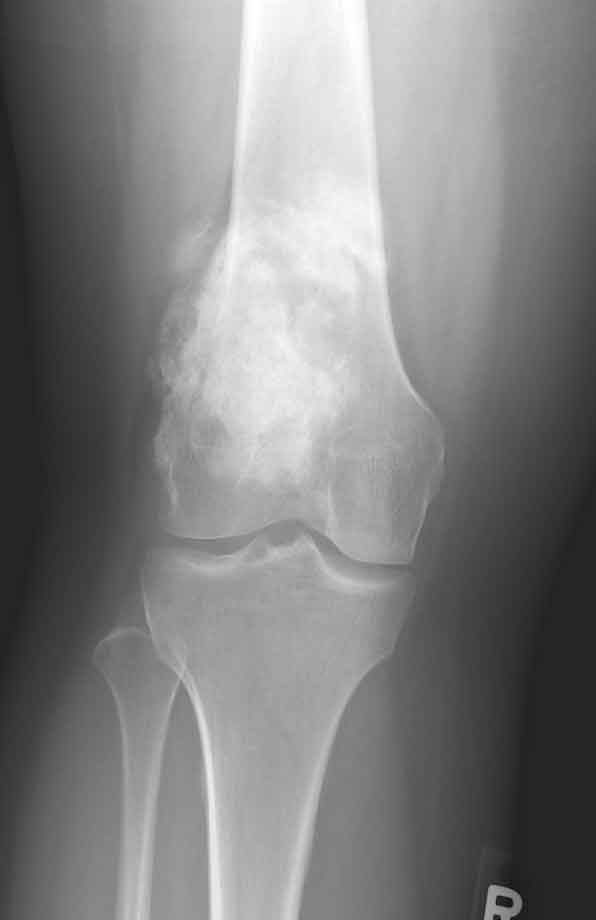

Imaging:

appearances;

destructive, poorly defined, mixed lytic and blastic

masses accompanied by cortical destruction and

tumor extension into soft tissue.

manifestations secondary to periosteal elevation (e.g.

Codman triangle) and periosteal reactive bone

formation.

perpendicular or radiating striations called "sunburst".